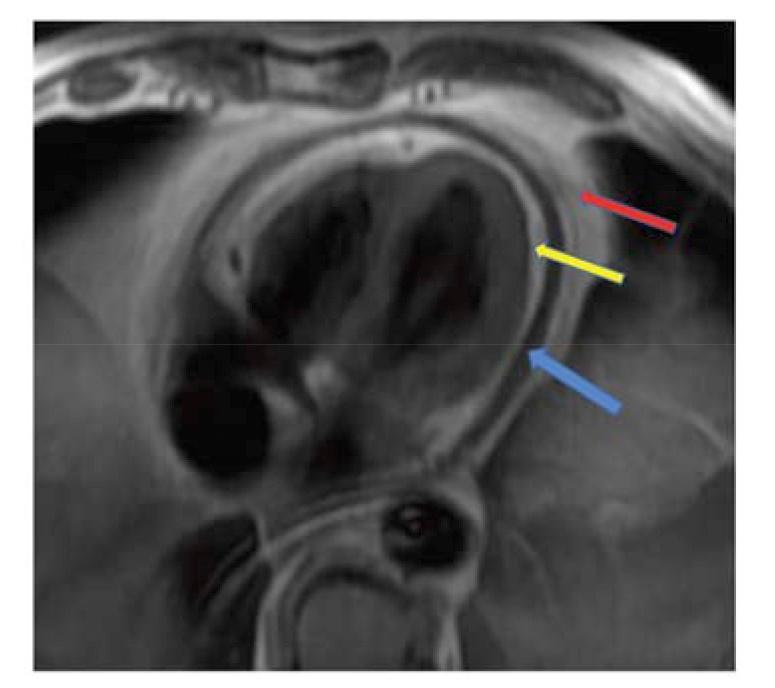

Herein we describe conventional and unique CMR approaches to provide an increased non-invasive understanding of the pericardium in health and disease including a novel method to diagnose constrictive pericarditis via radio-frequency tissue tagging by defining unique visceralparietal adherence patterns easily learned by the cardiologist and radiologist.

在此,我们描述了传统的和独特的CMR方法,以增强对健康和疾病状态下心包的非侵入性理解,包括一种通过射频组织标记诊断缩窄性心包炎的新方法,该方法可定义独特的心外膜-脏层粘连模式,心脏病专家和放射科医生可轻松掌握。